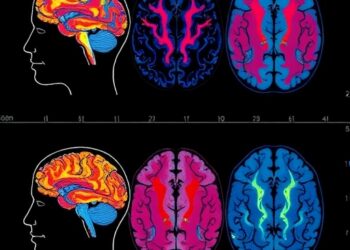

Neurophenotypes of Depression Revealed by Brain Patterns

In the pursuit of unraveling the complexities of Major Depressive Disorder (MDD), a recent breakthrough study has leveraged advanced neuroimaging ...